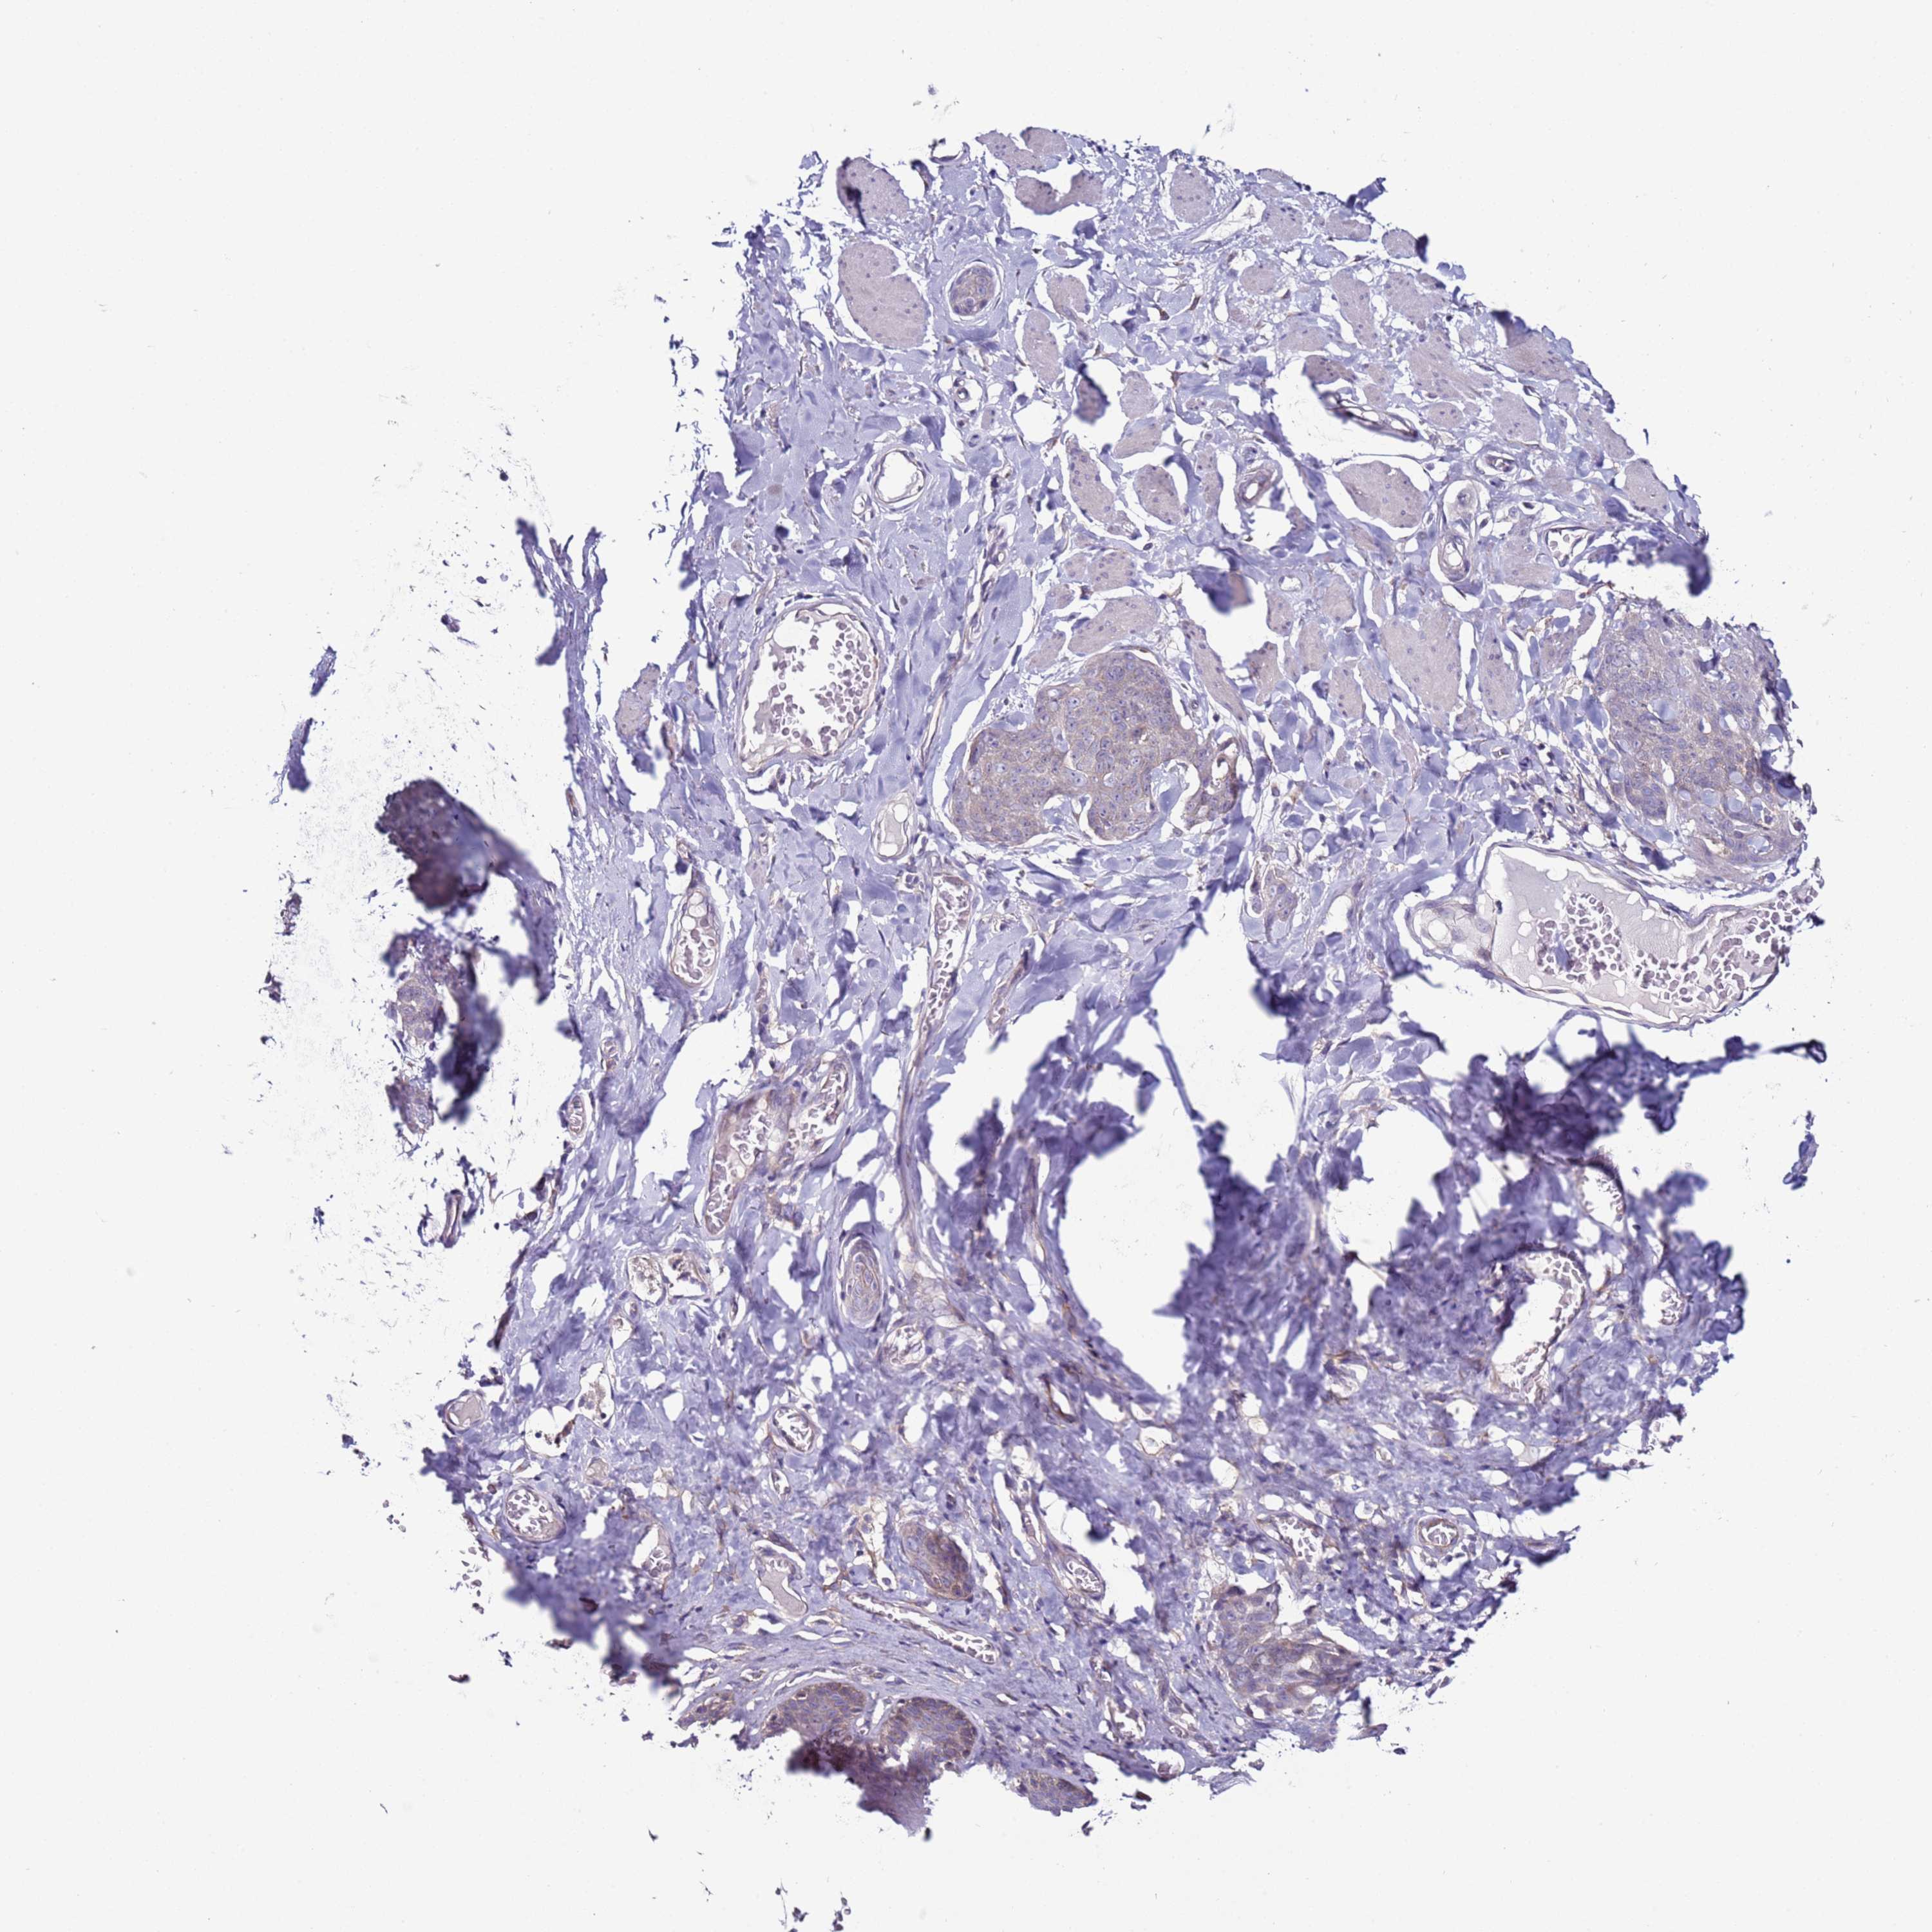

SKIN CANCER - Protein expressioni

A mouse-over function shows sample information and annotation data. Click on an image to view it in a full screen mode. Samples can be filtered based on level of antibody staining by selecting one or several of the following categories: high, medium, low and not detected. The assay and annotation is described here.

Each image is clickable and will lead to virtual microscopy that enables deeper exploration of all samples and also displays staining intensity scores, fraction scores and subcellular localization as well as patient and tissue information for each sample.

Antibody HPA039764

Basal cell carcinoma

Squamous cell carcinoma, NOS

Squamous cell carcinoma, metastatic, NOS

Squamous cell carcinoma in situ, NOS